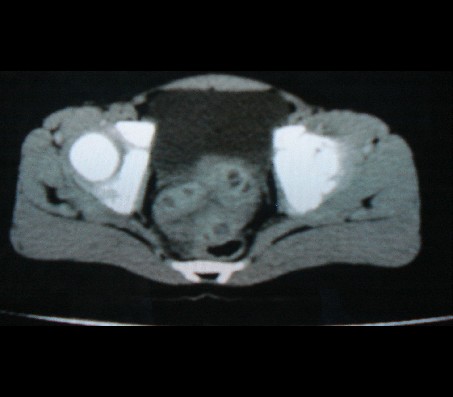

标题: PED0942:女性,8岁,B超提示盆腔病变,请会诊! [打印本页]

标题: PED0942:女性,8岁,B超提示盆腔病变,请会诊!

畸胎瘤

考虑畸胎瘤可能性大!

建议增强进一步检查除外畸胎瘤。

考虑畸胎瘤可能。

考虑畸胎瘤可能

考虑畸胎瘤可能性大.

考虑畸胎瘤可能性大。

畸胎瘤可能性大。

畸胎瘤可能性大!

考虑畸胎瘤可能大,建议进一步检查。